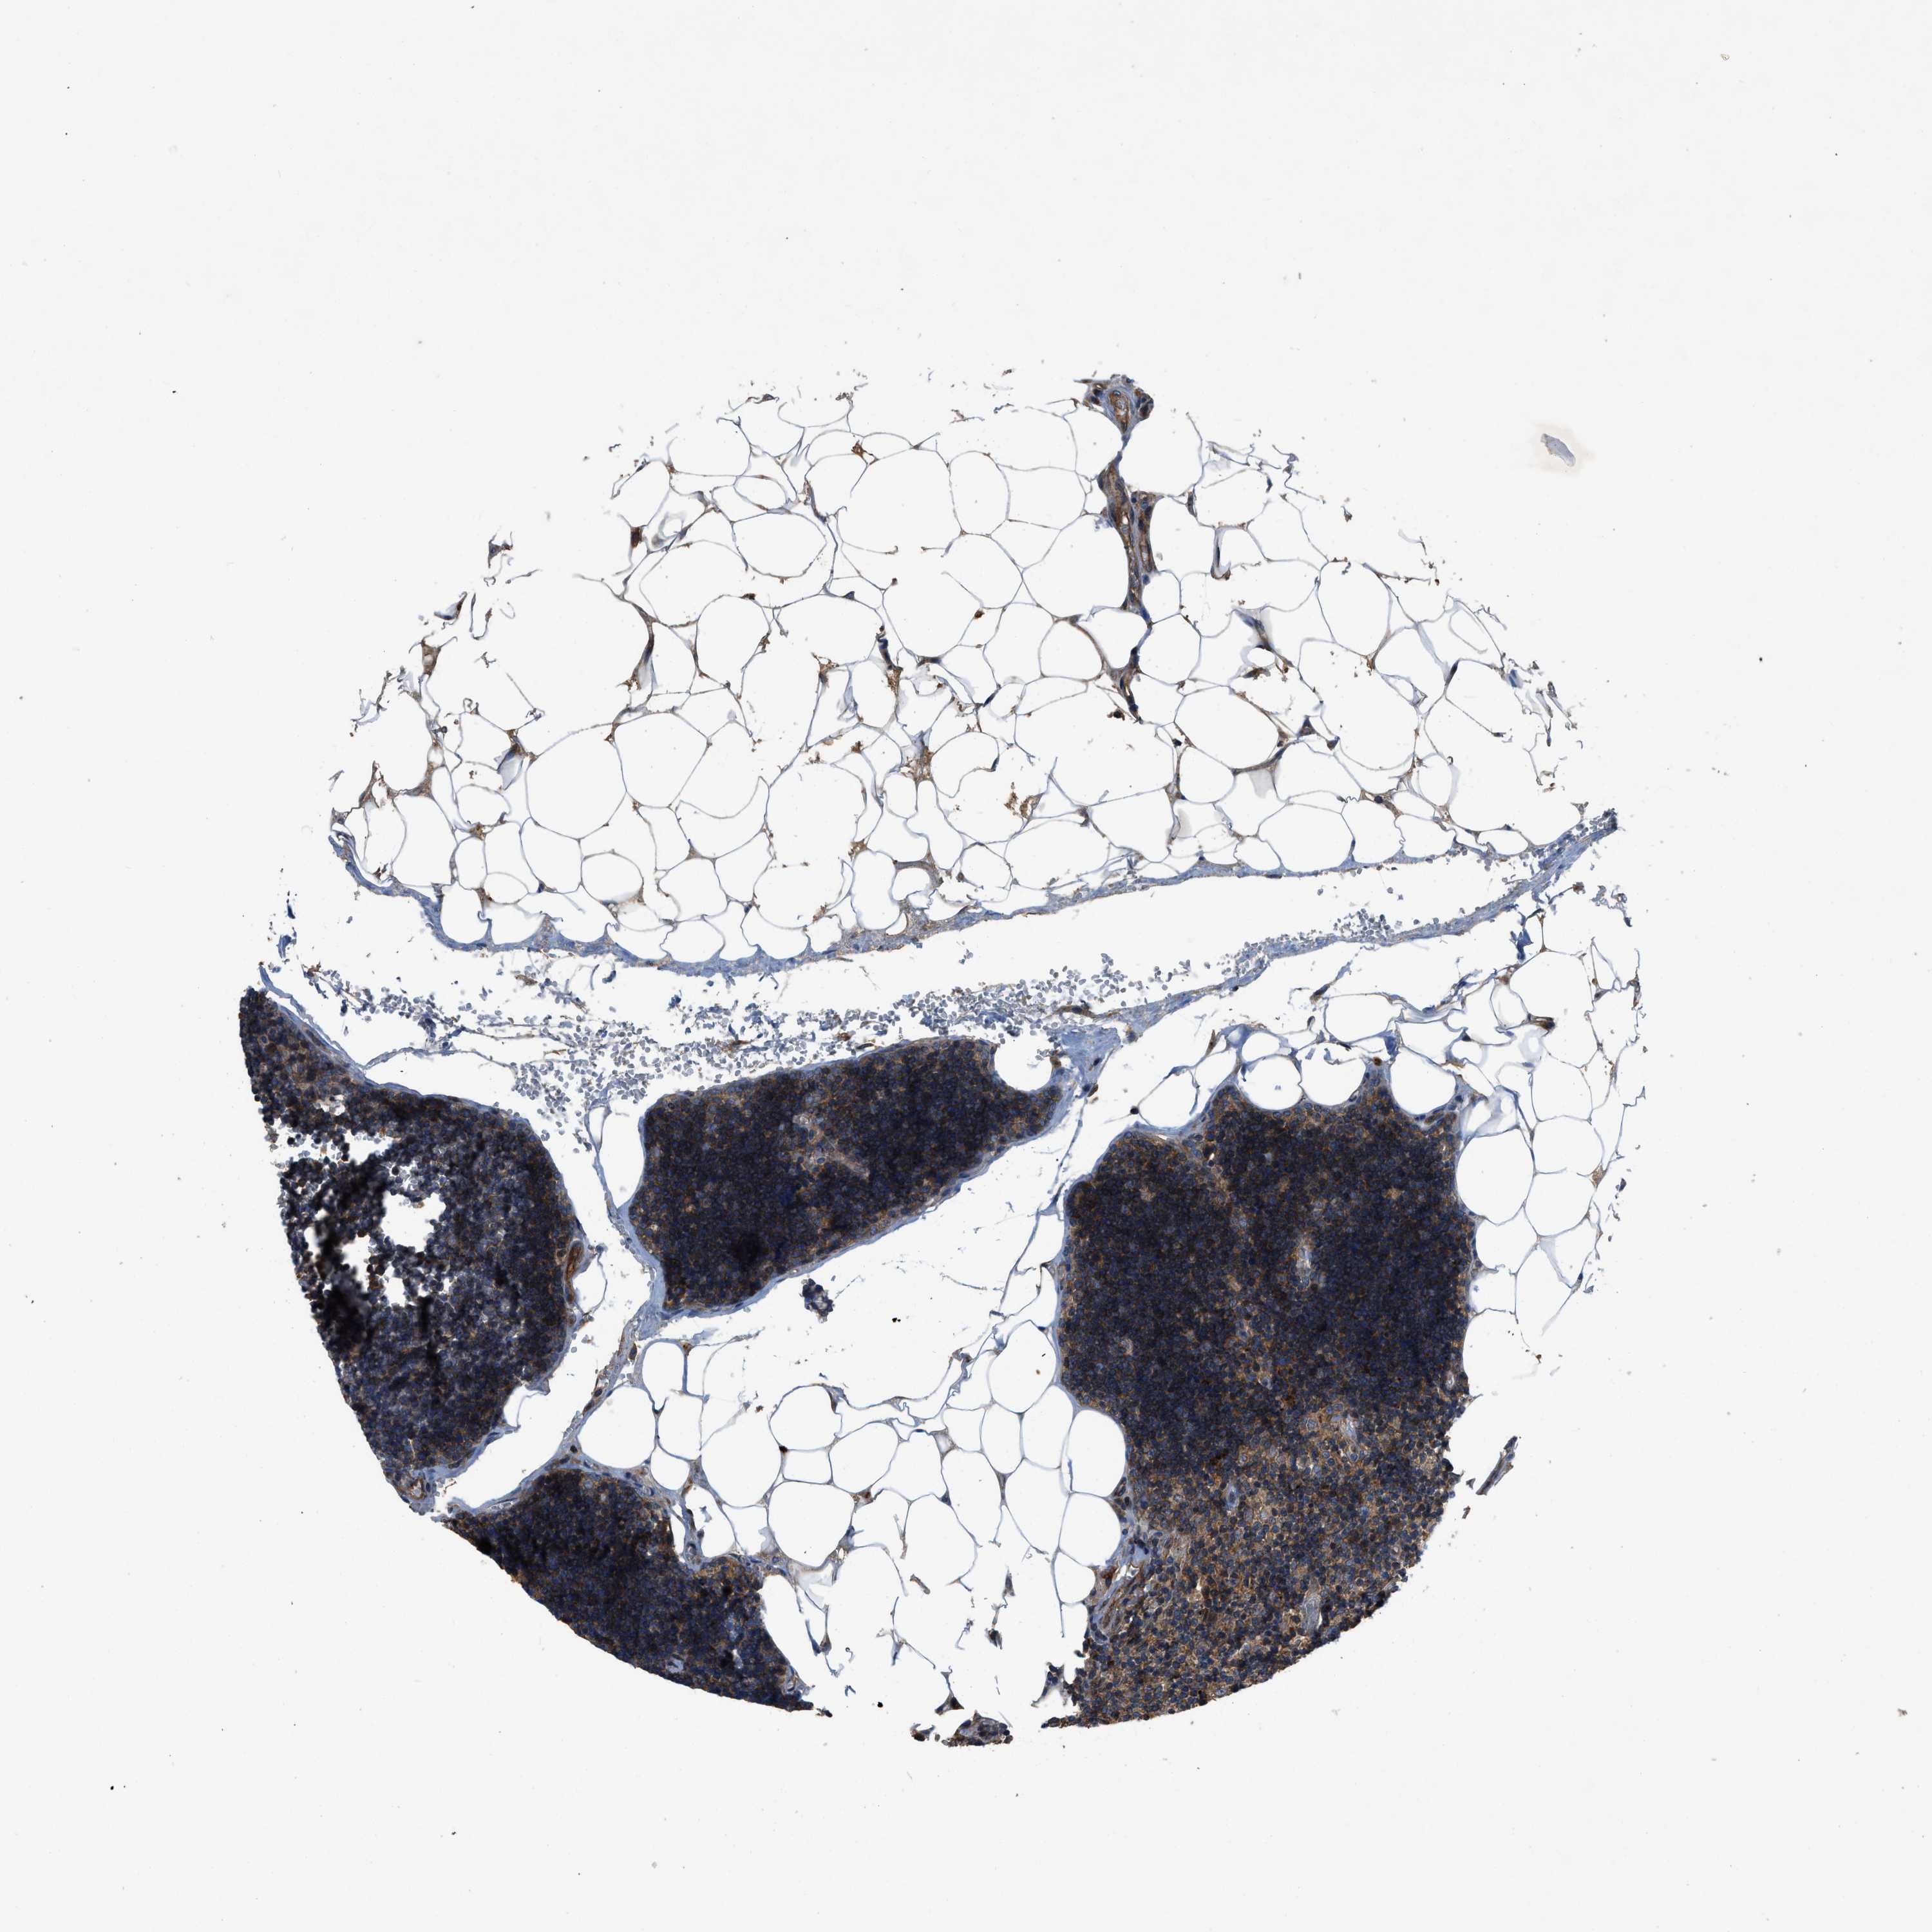

LYMPH NODE

Lymphoid tissue